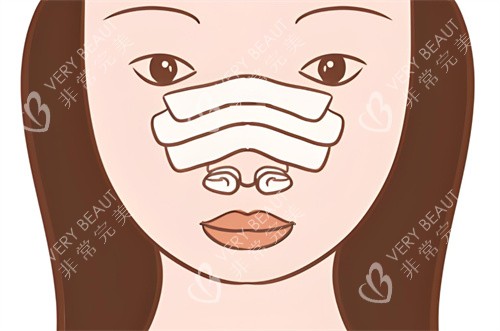

在手术过程中,他采用精细的操作手法,尽量减少对鼻部组织的损伤,确保术后修复快,并且能够呈现出自然逼真的结果。

此外,他还会根据患者的自身条件选择合适的材料,如自体软骨等,这些材料与人体组织相容性好,能够更好地融入鼻部,使术后鼻型更加自然。